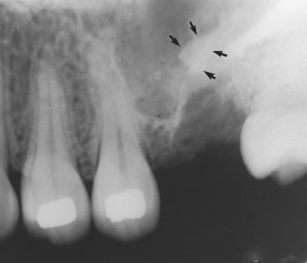

A root not removed with the tooth must be accounted for, due to the dangers of inhalation and infection. First look in the oral cavity, socket and adjacent tissues, next search extraorally and then take radiographs if necessary. Radiographs that are suitable for demonstrating a root in the antrum include periapical (Fig. 15.6) and oblique occlusal views or an OPT. The presence of a root canal confirms that a radio-opaque image represents a root.

Fig. 15.6 A root displaced into the maxillary antrum (arrows).